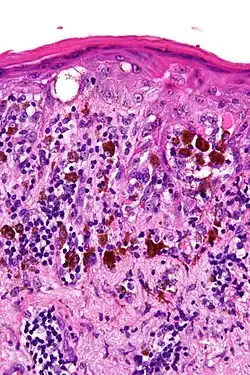

Light microscopy of lentigo maligna showing the characteristic atypical epidermal melanocytes. H&E stain.

Light microscopy of lentigo maligna showing the characteristic atypical epidermal melanocytes. H&E stain. -